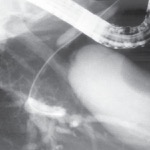

VANCOUVER, B.C.—Although the supine position for endoscopic retrograde cholangiopancreatography can be a reasonable choice in a number of circumstances, there were statistical advantages for the prone approach in a multicenter retrospective review.

“Prone ERCP positioning resulted in a higher desired duct cannulation rate, a shorter procedure time and a lower complication rate,” reported Shivani K. Desai, MD, a third-year internal medicine resident at Geisinger Medical Center, in Danville, Pa.

The rate of successful cannulation was higher (98.7% vs. 95.2%; P=0.0148), the procedure time shorter (22 vs. 32 minutes; P<0.0001) and the complication rate lower (1.3% vs. 3.4%; P=0.0017) among those who underwent ERCP in the prone instead of the supine position, Dr. Desai reported.

However, prone ERCP was associated with a longer fluoroscopy time (5 vs. 1.9 minutes; P<0.0001) and a greater likelihood of intraprocedural cardiovascular instability (64.5% vs. 41.4%; P=0.0035).